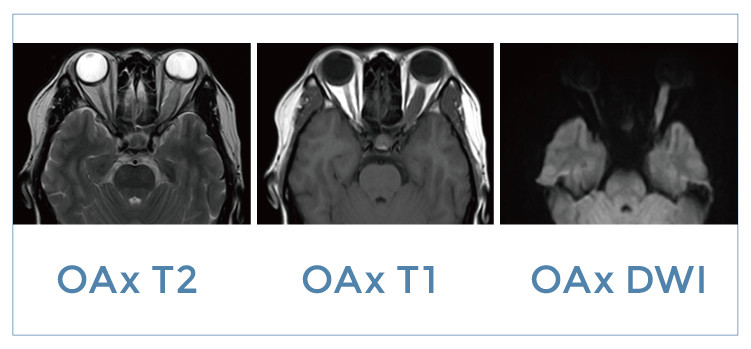

【朗润影像档案】20191018磁共振影像病例结果讨论

【朗润影像档案】磁共振影像病例分享(编号20191018)